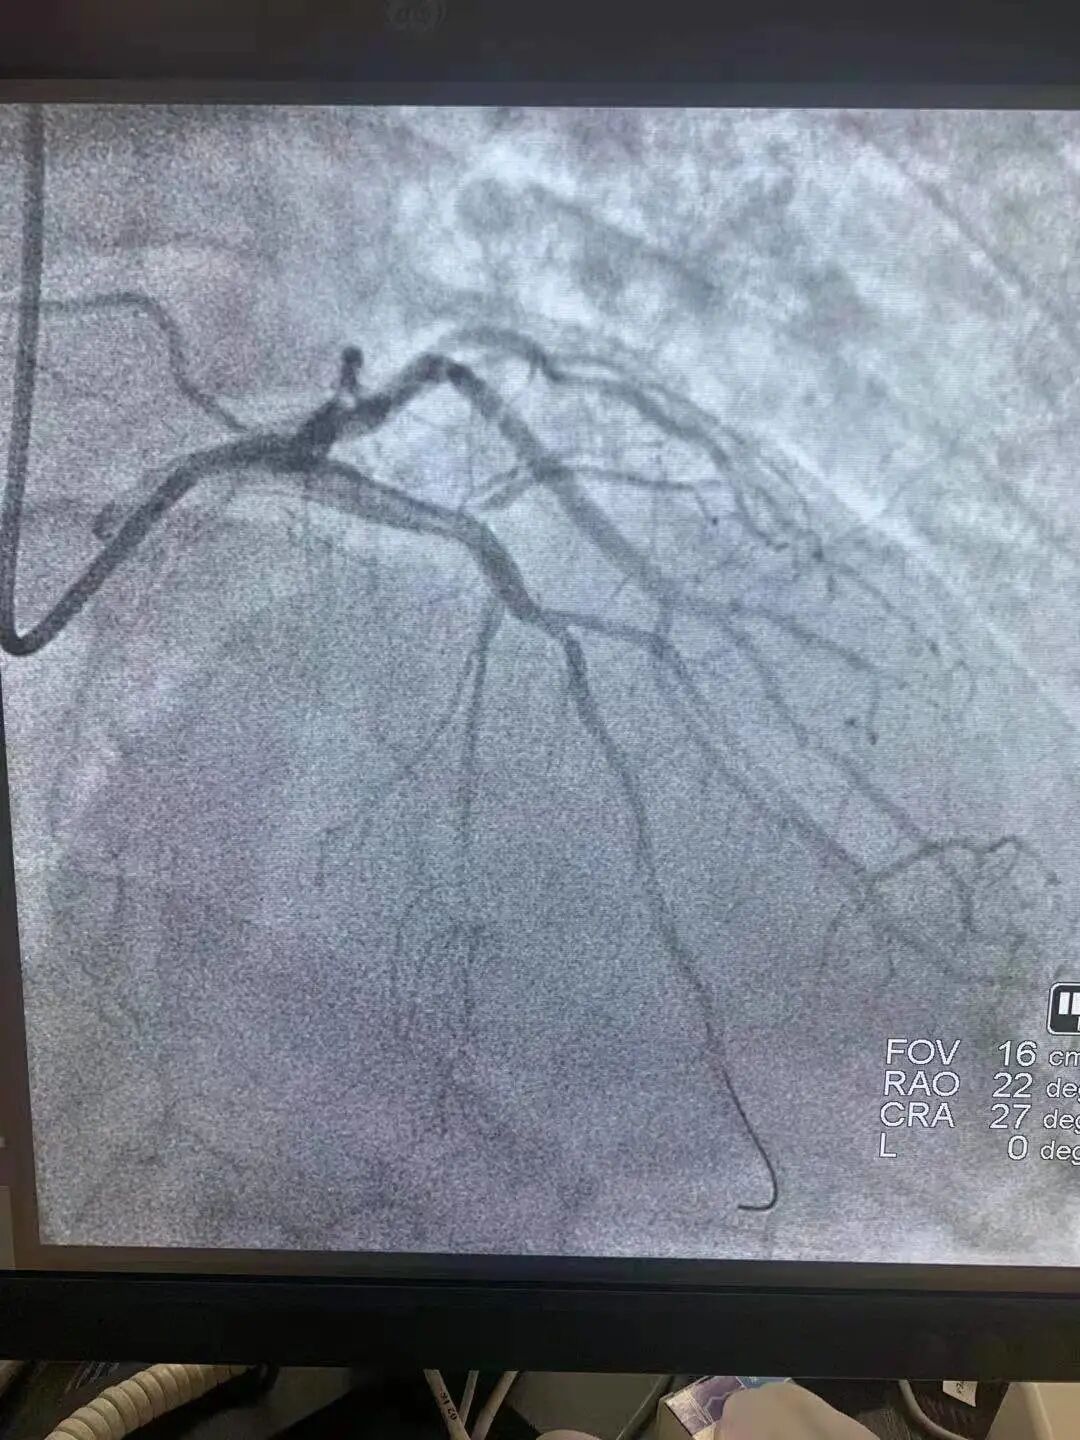

当日19时许,急救中心值班医师曲伟接诊后,通过为患者做心电图,初步判断为广泛前壁心肌梗死。随后通过造影发现患者右冠已经处于慢性完全闭塞状态,而且其前降支近段急性闭塞(心脏三支血管中最重要的一支),回旋支还有80%狭窄(此时患者心肌供血量不足正常情况的1/4),患者病情极其凶险,可谓生命垂危,命悬一线。值班医护人员立即启动绿色通道,刻不容缓地立即将患者送进手术室。

患者进入手术室,病情再次出现变化,血压降至70/40mmHg,脉搏氧饱和度73%,口唇紫绀,生命垂危,ICU、麻醉科、手术室医护人员组成一个与死神博弈的强大阵容,奋力抢救,密切配合。手术中,主刀的医生徐海佳和曲伟发现患者血栓负荷重,遂立马给予血栓抽吸,在多次抽吸出红色血栓后,又马不停蹄地为患者植入心脏支架,由此经过与死神长达1小时赛跑“抢人”,手术得以顺利完成。